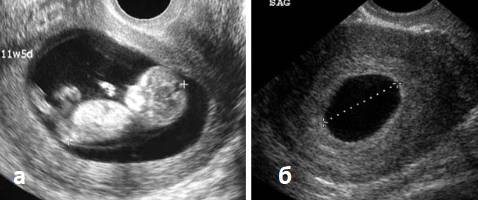

Отсутствие эмбриона внутри плодного яйца называется анэмбрионией. (рис. 3). При анэмбрионии формирование эмбриональных структур прекращается еще на этапе дифференцировки внутренней клеточной массы.

Рисунок 3. УЗИ на 7 неделе беременности: а – нормальный плод, б – анэмбриония

При этом по данным УЗИ плодное яйцо имеет меньшие размеры, чем в норме, эмбрион не виден. Также размеры плодного яйца могут соответствовать срокам беременности, эмбрион будет визуализироваться, но иметь очень маленькие размеры, сердцебиение отсутствует.

При УЗ-картине «замерший плод» плодное яйцо и эмбрион имеют обычную форму и размеров, но признаки жизнедеятельности отсутствуют. Если погибший плод долго находится в полости матки, то структура плодного яйца резко меняется, его контуры и форма становятся нечеткими, размеры матки отстают от срока беременности.